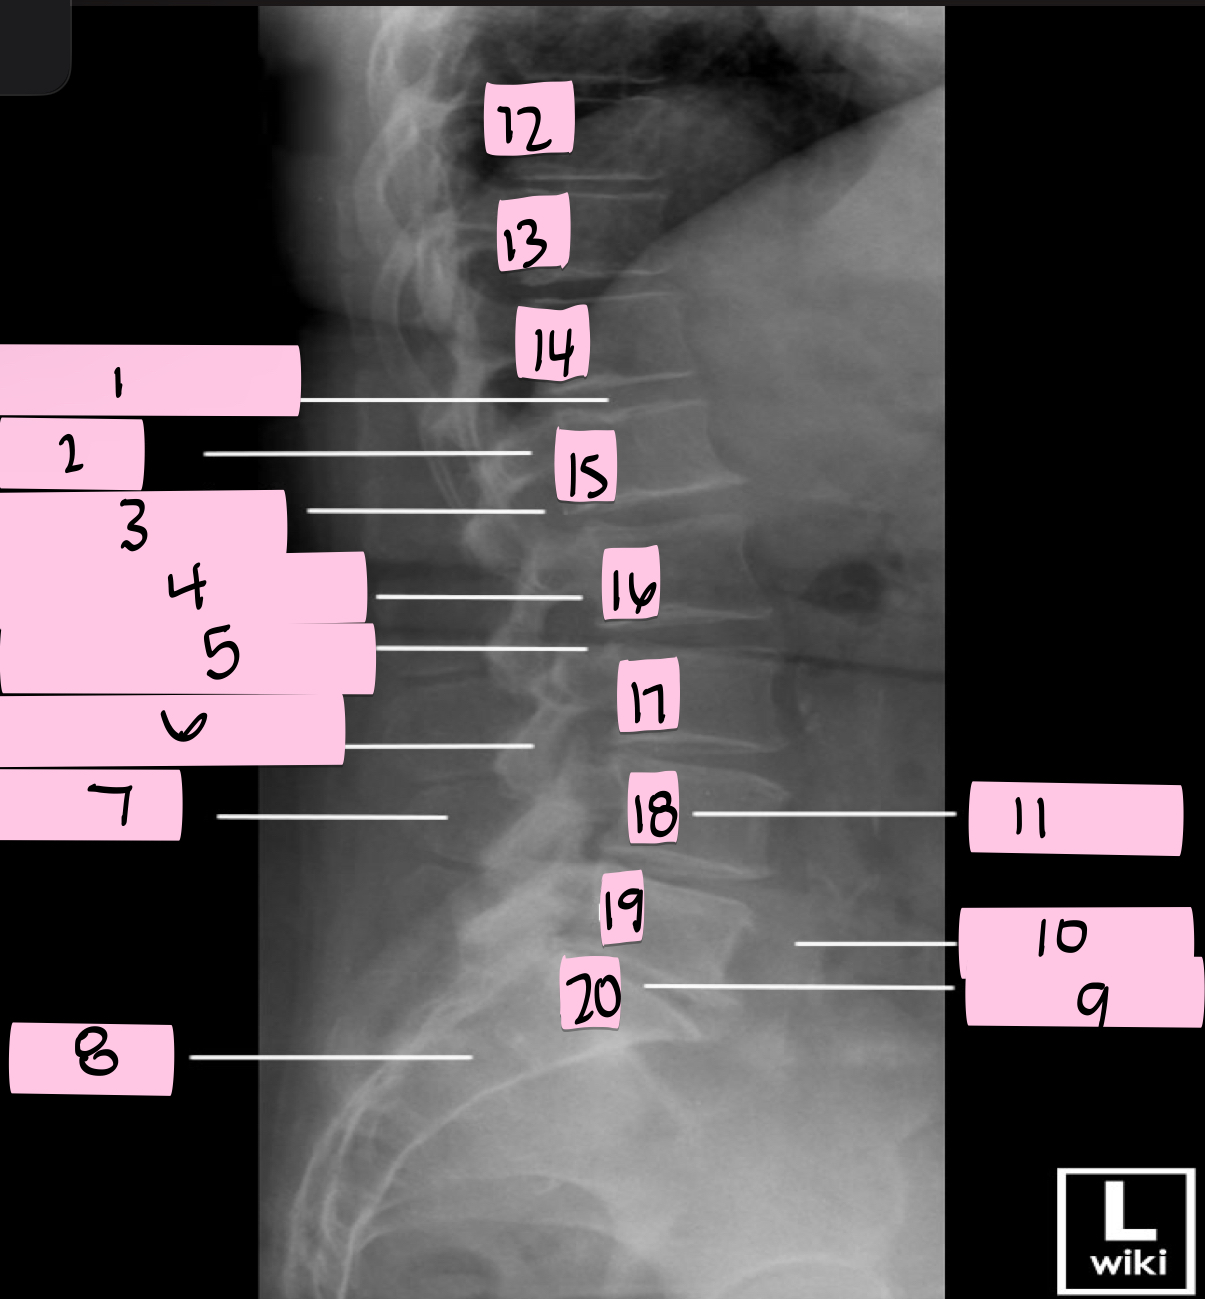

What is 1 pointing to?

Intervertebral disk

What is 2 pointing to?

Pedicle

What is 3 pointing to?

Intervertebral foramen

What is 4 pointing to?

Inferior vertebral notch

What is 5 pointing to?

Superior vertebral notch

What is 6 pointing to?

Inferior articular process

What is 7 pointing to?

Spinous process

What is 8 pointing to?

Sacrum

What is 9 pointing to?

L5 S1 joint

What is 10 pointing to?

Iliac crest

What is 11 pointing to?

Vertebral body (L4)

What is 12 pointing to?

T10

What is 13 pointing to?

T11

What is 14 pointing to?

T12

What is 15 pointing to?

L1

What is 16 pointing to?

L2

What is 17 pointing to?

L3

What is 18 pointing to?

L4

What is 19 pointing to?

L5

What is 20 pointing to?

S1